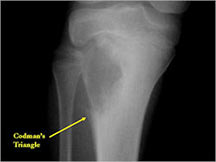

- May have Codman’s triangle and malignant appearing periosteal reaction in most cases

- Permeative lesion with indistinct border that is poorly marginated

- Osteolytic and expansile on X-ray with very little osteoid production